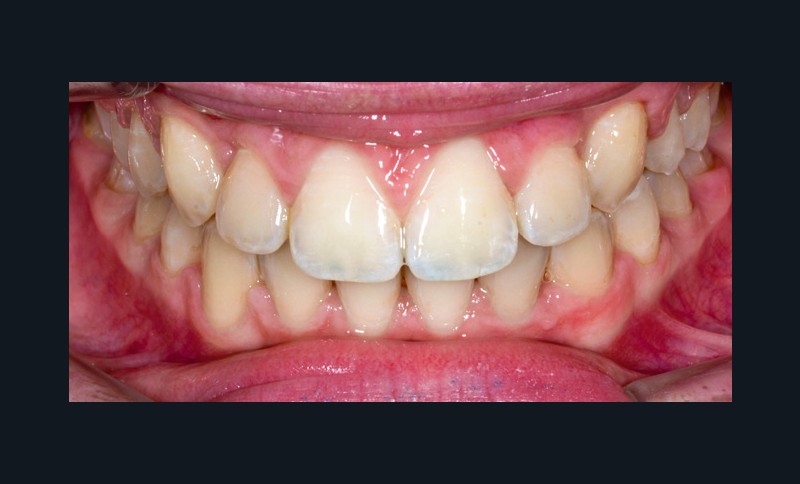

La patiente consulte à l’âge de 9 ans pour la malposition de ses incisives latérales maxillaires. Elle présente une occlusion de Classe I bilatérale sur un schéma normodivergent avec une dysharmonie dento-maxillaire en denture mixte. À l’arcade maxillaire, elle présente une endoalvéolie avec rotations mésiopalatines de 16 et 26.

Sur la radiographie panoramique, on observe une transposition des canines maxillaires en place d’incisives latérales, au contact des racines de 11 et 21.